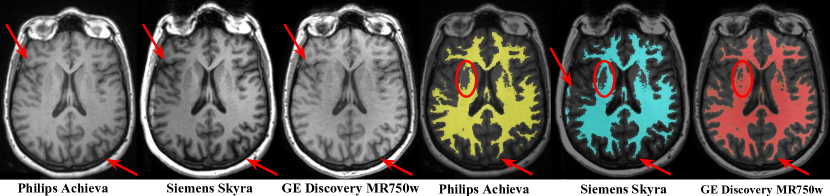

Large scale multi-site studies are of extreme importance in neuroimaging, both for research purposes and in clinical practice. Such studies face several challenges due to hardware- or center-related variability. It is well known that scanner-factors such as manufacturer, magnetic field and gradient non-linearly influence volume measurements [4, 14] obtained from structural Magnetic Resonance Imaging (MRI). At the image level, these factors are coupled with a high variability of intensities across patients and scanners, which can affect tasks like the segmentation of brain structures [16]. This effect is exemplified in Fig. 1, where three T1-weighted MR images from the same patient obtained on different scanners and their corresponding segmentations are represented.

Refer to caption

Figure 1: MR images from same patient in different scanners. Left side: T1-weighted images. Right side: white matter segmentations obtained using the same method.

To further validate the approach we test it in a dataset containing data from 10 MS patients as detailed in [7]. Each patient was scanned twice in three different 3T scanners: Philips Achieva, Siemens Skyra and GE Discovery MR450w. An example is depicted in Fig. 1. We observed that one of the patients was an extreme case, showing very enlarged ventricles. Given that the volumetric measurements in such a case are prone to errors and are considered unreliable, this patient’s data was discarded from further analysis.